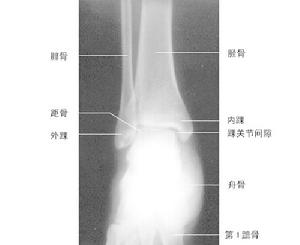

踝關節作者:唐農軒 范清宇

第二節 踝部檢查與診斷

二、影像學診斷